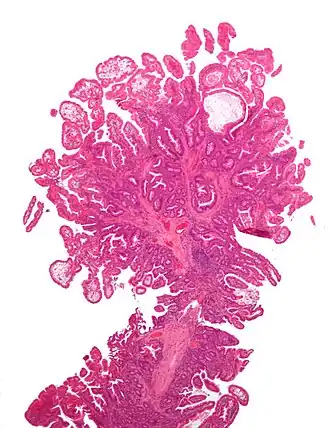

| Micrografia de um pólipo colorretal do tipo Peutz-Jeghers; coloração H&E. | |